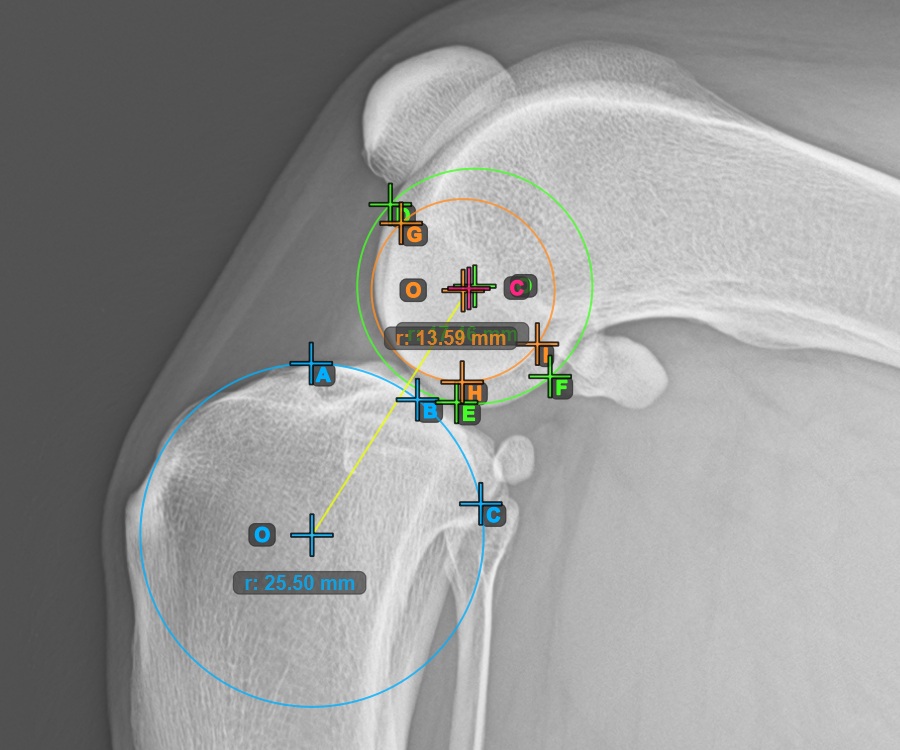

Mark the three points on the main condylus of the femoral bone (Condylus Femoris). Regardless of the order, make sure to mark the most cranial point, the most caudal point and the midpoint of the Condylus Femoris. A circle will be automatically constructed based on the three placed points.

The image below represents a typical placement of the three points on the first Condylus Femoris.